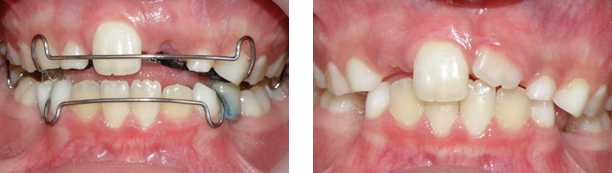

Al realizar el examen clínico, se observó ausencia del Organo Dental 21OD 21, en su lugar persistencia del OD 61 con destrucción coronaria y pólipo pulpar. Además, se identificó fístula en encía adherida vestibular a nivel de este mismo órgano dentario. Su contralateral OD 11 se observó totalmente erupcionado sin alteraciones (Figura 1). En el examen radiográfico se evidenció la presencia del OD 21 incluído, en un estadio de desarrollo de Nolla 8, ubicado en posición vertical y presencia del 61, el cual persiste en su posición conservando al menos un tercio de su raíz. No se observó fractura u otro tipo de afección al diente permanente (Figura 2).

Figura 2. Radiografía periapical inicial.